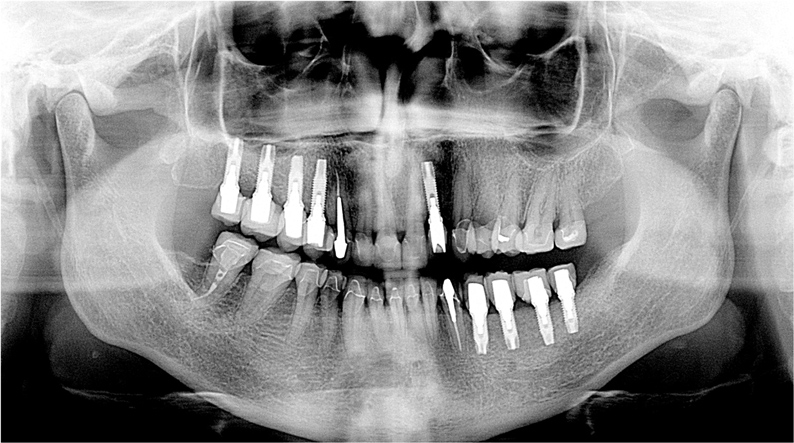

The 10-year postoperative panoramic radiograph (Figure 16) demonstrates the success of the reconstruction and the periodontal and dental implant foundation. The implants for the maxillary left quadrant are supported in regenerated bone where sinus grafting was performed, and the mandibular right canine and bicuspids have been stable with gain of clinical attachment and radiographic suggestion of bone fill after the periodontal surgical care. There is mild recession, especially for the maxillary anterior abutments, after 10 years of maintenance; however, the case is remarkably stable and healthy radiographically and clinically (Figure 17). There is minimal sulcular depth for the previously deep pocket on the distal aspect of the mandibular right canine (Figure 18). The results demonstrate the potential for longevity following periodontal-prosthodontic principles of treatment.

Once the healing was complete for the periodontal and dental implant procedures (Figure 22 and Figure 23), the final tooth preparations were completed and final impressions were made; records, including the electronic pantographic record, were then obtained. The treatment wax was used (Figure 24) to secure the patient’s approval of the esthetic design and to evaluate the esthetics and plan for the final prosthesis, including the cross-bite. The vertical dimension was raised, the facial anatomy was checked, and her speech and esthetics were checked by filming the patient and viewing facial profiles. Next, the implant abutments were made (Figure 25). In this case, metal–ceramic abutments were chosen; they were tried on before beginning the fabrication of the final restorations. These monolithic ceramic materials use lithium disilicate, which can result in a restoration with excellent biomechanical and esthetic properties (Figure 26 and Figure 27). The restorations were observed; the radiographs show the implants placed in the regenerated bone (Figure 28).

Figure 16 10-year results of periodontal–implant–prosthodontic reconstruction.

Figure 16

Figure 21 Panoramic radiograph showing the advanced bone loss for the fractured mandibular left second bicuspid. Pneumatization of the maxillary right sinus is noted, as is supra-eruption of posterior teeth.

Figure 21

Figure 28 The postoperative panoramic radiograph.

Figure 28